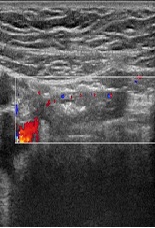

Tuberculosis in Children: Diagnosis of A Case Involving Isolated Lymphadenitis

Hady Tall*, Amadou Sow, Dibor Niang, Modou Mbacke, Samba Niang, Ibrahima Diagne